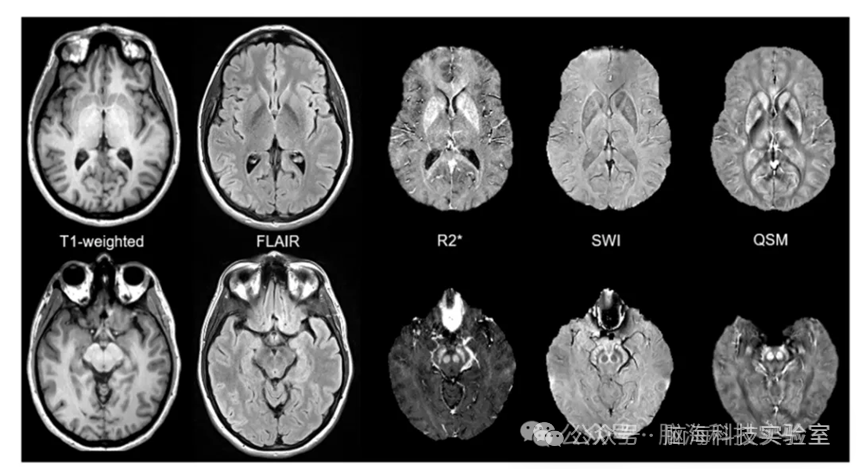

该文综述了定量磁敏感成像(QSM)在帕金森病(PD)中的应用。帕金森病是一种常见的神经退行性疾病,其发病机制尚未完全明确,但铁代谢紊乱与脑内特定区域的铁积累被认为与疾病进展密切相关。QSM作为一种新兴的MRI技术,能够非侵入性地量化脑内铁含量,为研究铁在PD病理中的作用提供了重要手段。文章详细介绍了铁在帕金森病中的作用机制,包括铁在黑质中的积累以及其与α-突触核蛋白聚集的关系,并探讨了铁催化的氧化应激反应(如铁死亡)对神经退行性的影响。此外,文章还回顾了多种铁敏感的MRI技术,特别是QSMPD诊断和疾病监测中的潜力。尽管QSM在过去十年中取得了显著进展,但仍面临一些挑战,如图像伪影、组织几何依赖性等。未来需要开展多中心研究,以开发出更稳健、可解释且具有疾病特异性的生物标志物,用于监测PD的疾病进展。

黑质铁与帕金森病图

易感性敏感对比度图